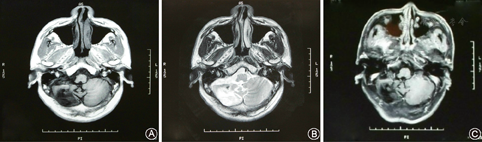

头颅MRI检查:小脑血管母细胞瘤术前MRI检查(1997年8月,图1)示右侧小脑半球见一椭圆形囊性病灶,大小约5.5 cm×4.0 cm,囊壁内见一直径约1.0 cm壁结节,增强扫描壁结节强化明显,大囊未见强化,囊壁清晰。术后MRI(2009年12月,图2)检查示右侧小脑血管母细胞瘤术后改变,右侧枕叶小片陈旧性软化灶,局部小脑内片状异常信号影,边界不清,信号欠均匀, T1WⅠ为低信号,T2WⅠ为高信号,增强未见明显异常强化,未见肿瘤残留或复发。

A.T1像右侧小脑半球不规则囊状低信号灶;B.T2像囊状高信号灶欠均匀,边界不清,脑室受压不明显;C.增强扫描未见明显异常强化,未见肿瘤残留或复发